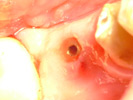

Endodonzia